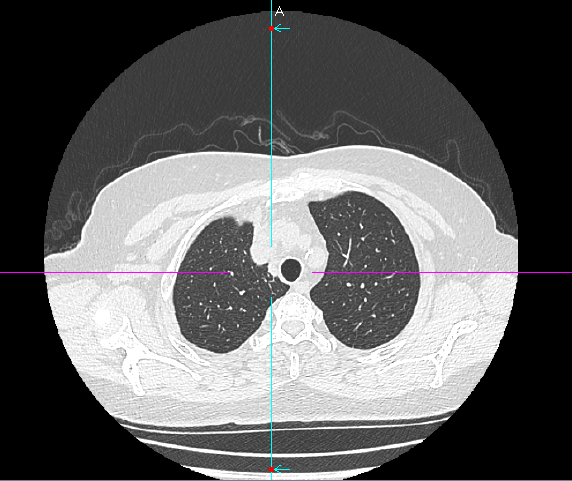

数月前,66岁的龚女士在肺癌术后随访复查中,胸部CT报告显示其右上肺新发实性结节一枚,并由刚开始发现时的5mm逐步增大至10mm。更棘手的是,这个结节位于右肺上叶尖段的纵隔胸膜下,位置极其“刁钻”。面对这份报告,患者龚女士陷入了深深的焦虑。因为其7年前因右中肺肿瘤行右中肺癌根治术,对于新发的实性结节为何种性质,是新发肺恶性肿瘤或是良性病变,亦或是原肺癌复发转移,目前均不能明确。辗转多家医院,得到的建议多为“定期观察,等待变化”或考虑创伤较大的传统穿刺活检,但结节位置非常深,单纯CT引导下定位穿刺很难精准到达,且需穿行的肺组织较多,创伤较大。

胸外科马海涛主任团队对龚女士的病情进行了深入细致的评估:结节虽小,但形态学特征具有风险,且结节逐步增大,结合既往肺癌病史,考虑肿瘤复发可能,“定期观察”方案会让患者持续承受心理煎熬。然而,传统的CT引导下经皮肺穿刺定位,对于如此深部、微小的结节,极易导致气胸、出血等并发症,风险极高。